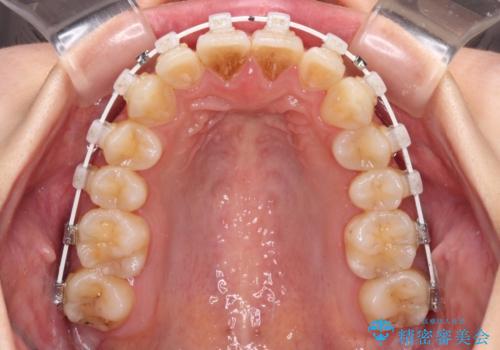

- 矯正装置

- 審美装置

- 1年5ヶ月

- 前歯の突出感を気にして来院された患者様です。

左右ともに奥歯の咬み合わせが上顎前突となっており、上顎前歯が飛び出している状態でした。

奥歯の咬み合わせ改善が必要であるため、マウスピース矯正より確実に達成のできるワイヤー矯正にて治療を行うこととしました。